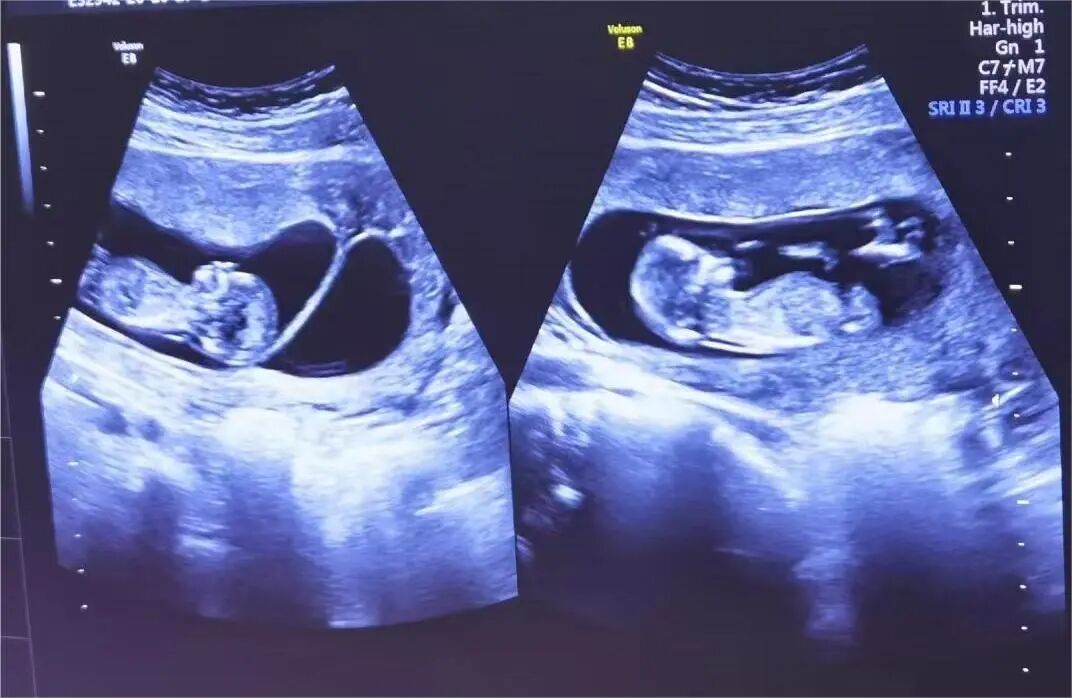

4月2日,贵州航天医院第55次晨读会由我院超声科医师敖春庆作学术交流,她以“中孕期产前超声筛查技术”为题,详细讲解了进修学习的成果,分享了科室实际开展的病例,阐述了未来的工作计划与展望,并结合典型病例图文分析等形式,强调了中孕期产前超声筛查的重要意义。 超声科专家简介 吴艳辉 中共党员,超声科学科带头人、主任,主任医师 临床擅长:从事超声诊断工作约30年,对心血管、小器官超声、超声引导下介入等具有丰富的临床经验。 骆科美 中共党员,超声科副主任医师 临床擅长:从事超声诊断工作33年,对胎儿心脏及颅脑、妇产超声、盆底超声等诊断具有丰富的临床经验。 胡大海 超声科副主任医师 临床擅长:从事超声工作17年,对心血管、外周血管、浅表器官超声诊断等具有丰富的临床经验。 刘 敏 超声科副主任医师 临床擅长:从事超声诊断工作20余年,对妇产科超声、心脏血管超声诊断具有丰富的临床经验。 敖春庆 超声科主治医师 临床擅长:对腹部、泌尿、妇科等超声诊断具有丰富的临床经验。 超声科简介 基本情况 贵州航天医院超声科配备多种超声检查设备(飞利浦彩超(IU-22、IU-Elite、HD11、Q5、Q7),迈瑞超声I9、DC-6、DC-8、GE-E8及床旁机,彩色超声诊断仪等),设有心血管诊室、妇产科诊室、腹部诊室、浅表小器官等检查室。 专科特色 四肢血管超声检查、双胎产前筛查及超声监护、超声造影检查技术、介入超声临床应用、经颅脑实质超声辅助筛查诊断帕金森病、女性性早熟超声诊断、盆底超声检查等。 NT超声检查 超声介入引导 肝脏超声造影 甲状腺造影 颅脑超声帕金森辅助检查 乳腺超声造影 上肢动静脉造瘘超声检查 双胎超声筛查 下肢血管超声检查 右心造影 诊疗范围 科室业务覆盖腹部、泌尿、妇科、产科(常规、NT筛查、III级筛查超声检查及高危妊娠监护)、成人心脏、外周血管、浅表器官(包含甲状腺、乳腺、阴囊、眼睛等)、颅脑(小儿颅脑、成人颅脑)、小儿肺超、造影、盆底、腹直肌、肌骨神经等检查及各种介入引导。 end